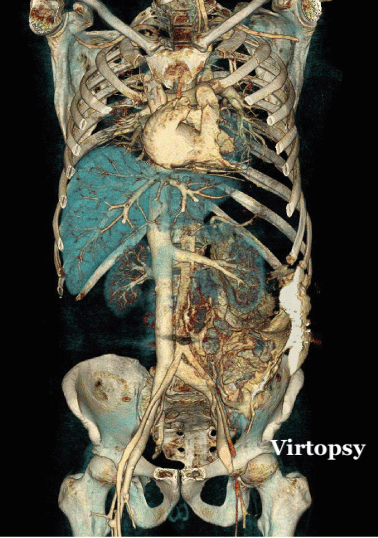

L'imagerie médicale est aujourd'hui directement impliquée dans la médecine légale et la pratique de l'autopsie. Le terme de Virtopsy est ainsi désormais largement répandu et favorise une collaboration étroite entre les praticiens de médecine légale et les radiologues.

L'imagerie forensique est devenue, au fil des ans, une discipline très prisée des médecins légistes pour les assister dans leur discipline. Des reconstructions en trois dimensions d’images scanographiques acquises post-mortem permettent, par exemple, de reconstituer les trajets lésionnels provoqués par des balles, ce qui constitue un type de pièces à conviction à présenter devant une cour de justice.

Une revue scanographique exhaustive de tous les organes traversés par le projectile

Les trajectoires balistiques sont ici évaluées au scanner dans les 3 plans de l’espace, selon la méthode utilisée par les médecins légistes dans les rapports d’autopsie, et d'après des éléments sémiologiques comme les défauts dans le revêtement cutané, associés à des bulles d’emphysème sous-cutanées par exemple. Le trajet hématique se manifeste, d'autre part, par une hyperdensité linéaire au sein des masses musculaires ou du parenchyme cérébral. Un trajet bulleux dans les organes pleins et les poumons sont également des critères d'évaluation précis, de même que le descriptif lésionnel de l’encéphale aux pieds, en analysant différents axes artériels et veineux (aorte thoracique et abdominale, troncs artériels supra-aortiques, mésentère, veine cave inférieure), ainsi que chaque organe, chaque segment osseux, avec latéralisation systématique et recherche d’épanchement au contact des organes pleins intra-abdominaux.

Les trajectoires balistiques sont ici évaluées au scanner dans les 3 plans de l’espace, selon la méthode utilisée par les médecins légistes dans les rapports d’autopsie, et d'après des éléments sémiologiques comme les défauts dans le revêtement cutané, associés à des bulles d’emphysème sous-cutanées par exemple. Le trajet hématique se manifeste, d'autre part, par une hyperdensité linéaire au sein des masses musculaires ou du parenchyme cérébral. Un trajet bulleux dans les organes pleins et les poumons sont également des critères d'évaluation précis, de même que le descriptif lésionnel de l’encéphale aux pieds, en analysant différents axes artériels et veineux (aorte thoracique et abdominale, troncs artériels supra-aortiques, mésentère, veine cave inférieure), ainsi que chaque organe, chaque segment osseux, avec latéralisation systématique et recherche d’épanchement au contact des organes pleins intra-abdominaux.

Cette technologie confère une aide précieuse aux médecins légistes pour déterminer les causes d'un décès, par l'étude d'un trajet balistique, l'évaluation de l'état d'un squelette après un accident ou l'identification, par angioscanner post-mortem, des conséquences d'une hémorragie massive. Elle est également déterminante pour l'identification des corps après une catastrophe naturelle ou industrielle. L'Institut Médico-légal du CHU de Tours a fait le choix, en fin d'année 2018, de s'équiper d'un scanner de dernière génération afin d'améliorer la qualité du service rendu à la justice en matière d'autopsie médico-légale. Il s'est tourné, pour ce faire, vers Fujifilm et a fait l'acquisition de son nouveau scanner FCT Speedia 64 barrettes. Il est devenu ainsi le premier institut médico-légal français à s’équiper d’un scanner Fujifilm.